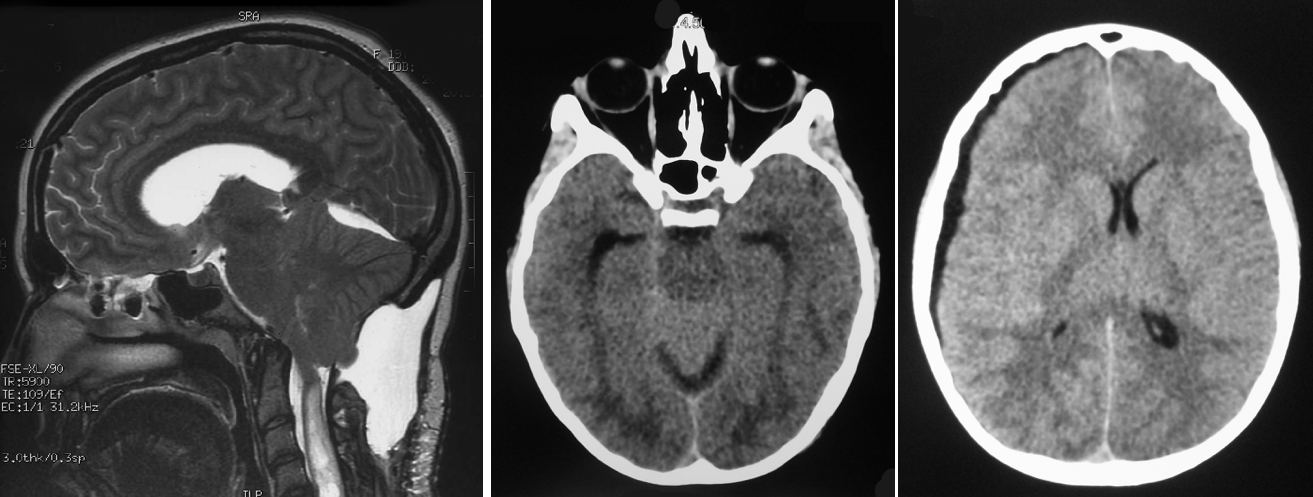

par ailleurs, avant de décider d’un abord de la charnière cranio-cervicale, il est indispensable de s’assurer :

- de l’absence d’hydrocéphalie

- de l’absence de malformation osseuse de la charnière cranio-cervicale

- dissection arachnoïdienne permettant de s’assurer de la bonne communication des ventricules avec les citernes

- il existe souvent une gliose importante (F) de la pointe des tonsilles qui atteste de leur effet compressif